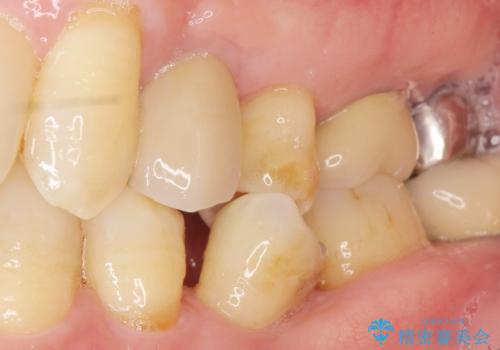

歯がわれた 抜歯してインプラント 50代男性

- 歯ぐきの腫れと痛みを主訴に来院された患者様です。

精査したところ、歯が割れており保存不可能な状態であったためやむなく抜歯しました。

患者様のご希望によりインプラント治療を行いました。